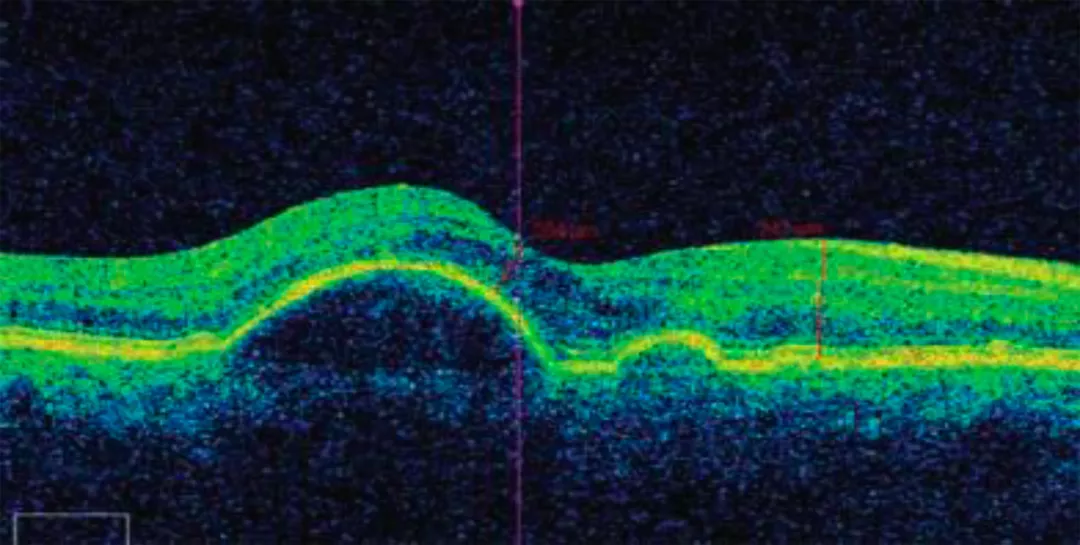

Для подтверждения диагноза проводят офтальмоскопию при расширенном зрачке, цветное фотографирование, флюоресцентную ангиографию (ФАГ), оптическую когерентную томографию (ОКТ) и ОКТ-ангиографию (ОКТ-А). ОКТ позволяет детально визуализировать морфологию сетчатки (рис. 1–3), а ОКТ-А — провести ее углубленный анализ (рис. 4).

ОКТ макулы пациента с отслойкой пигментного эпителия

Рисунок 1. ОКТ макулы пациента с отслойкой пигментного эпителия8

Примечание. Сетчатка возвышается над хориоидеей в виде правильного купола. Изменений в слое хориокапилляров нет. Пигментный эпителий визуализируется как сплошная линия. Полость между ПЭС и слоем хориокапилляров заполнена оптически прозрачным содержимым. Архитектоника слоев нарушена минимально.